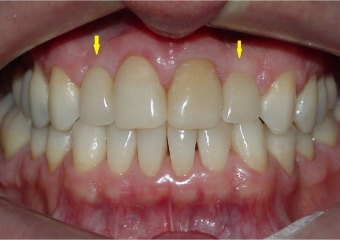

Sorriso inicial